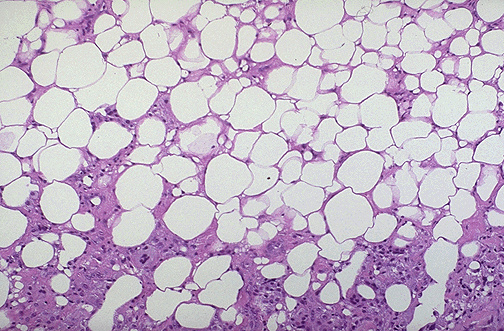

| This is fat necrosis of the breast. The most common etiology is trauma. It can be a localized, firm area with scarring that can mimic a breast carcinoma. Microscopically, however, fat necrosis consists of irregular steatocytes with no peripheral nuclei and intervening pink amorphous necrotic material and inflammatory cells, including foreign body giant cells responding to the necrotic fat cells. |